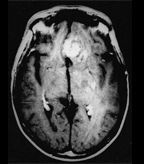

Recurrent glioblastomas produce expansile foci of contrast enhancement. These imaging features are nonspecific, however, and may be due to radionecrosis rather than recurrent tumor.

Glioblastoma multiforme is an aggressive and invasive tumor. Although there have been advances in surgical techniques, as well as advances in chemotherapy and radiotherapy approaches, the cancer remains difficult to treat. The median survival is only 15 months.